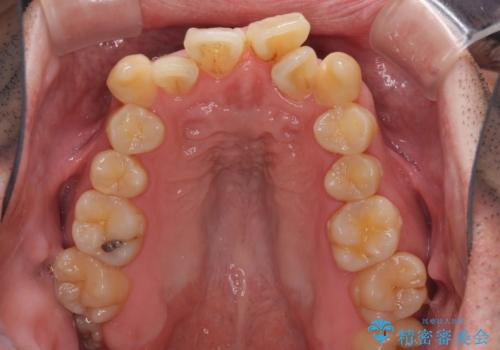

ものが挟まる 著しい叢生を解消 ワイヤー装置による抜歯矯正

- 前歯のデコボコを気にして来院された患者様です。

叢生の解消とともに、前方に張り出した上顎前歯を引っ込めることを目的とし、上下左右の第一小臼歯4歯を抜歯をしてワイヤー矯正により治療することとしました。

治療開始直後は、あっという間に歯列が整い、すぐに終わるのではないかと思われましたが、治療の後半にブラックトライアングル解消のための処置を行ったため、当初予定していた2年半ほどの期間を要することとなりました。